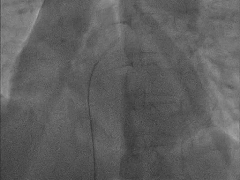

手术策略:右心室造影+卵圆孔封堵术。

手术操作

输送轨道建立

左盘展开

将输送系统整体回撤贴靠间隔

右盘展开

双盘扣合住房间隔

锁定前牵拉测试

封堵器稳定夹持在房间隔两侧

成型锁定

封堵器锁定成型,DSA下牵拉测试,造影确认无残余分流

释放封堵器

剪线并抽出线后解脱钢缆